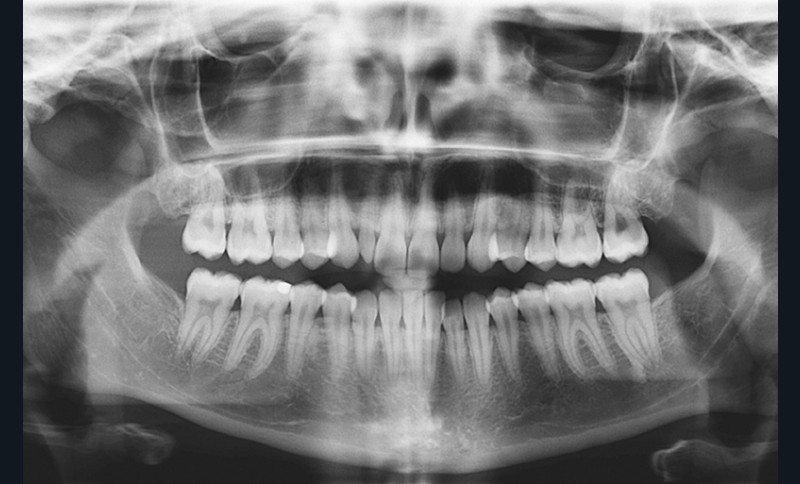

La radiographie panoramique révèle la présence de toutes les dents définitives, à l’exception des dents de sagesse, extraites (fig. 7).